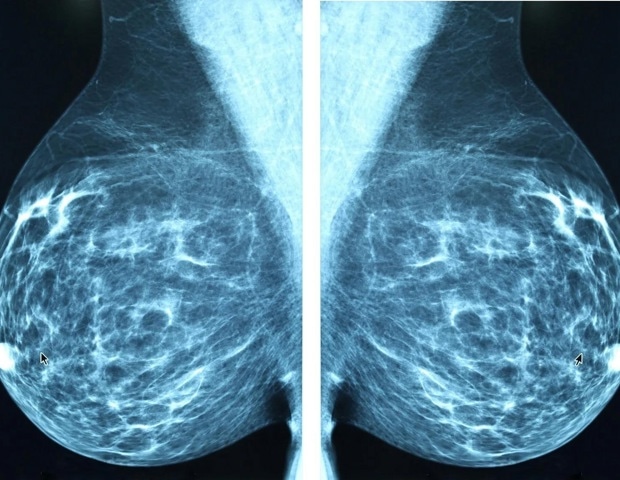

HR-положительный, HER2-отрицательный рак молочной железы Это наиболее распространенный подтип рака молочной железы, и по меньшей мере 50% всех рецидивов этого подтипа происходят более чем через пять лет после постановки диагноза, объяснил Джозеф А. Спарано, доктор медицинских наук, руководитель отделения гематологии и онкологии онкологического центра Маунт-Синай-Тиш. Показатель рецидивов Oncotype DX (ODX) по 21 гену, унимодальный молекулярный тест, который предоставляет прогностическую информацию об отдаленном рецидиве и прогностическую информацию о пользе химиотерапии, широко используется в клинической практике, хотя его способность прогнозировать рецидив после пятилетней отметки ограничена, отметил Спарано.

Нашей целью была разработка нового диагностического теста, который обеспечивает лучшую прогностическую оценку риска рецидива, в том числе позднего. риск рецидива путем изучения образцов опухолей из исследования TAILORx. Мы разработали модель искусственного интеллекта, которая оценивает как изображения оцифрованных слайдов, используемых для рутинной патологоанатомической оценки, так и молекулярные и клинические характеристики рака молочной железы, чтобы предоставить лучшую прогностическую информацию о риске рецидива рака на срок до 15 лет, включая ранний рецидив в течение пяти лет после постановки диагноза и поздний рецидив через пять лет».

Исследовательская группа использовала оцифрованные изображения тканей и данные экспрессии молекулярной РНК из 4462 образцов опухолей, а также соответствующие клинические данные участников исследования TAILORx. Эти данные были использованы для обучения и проверки нескольких моделей риска. Прогностические характеристики моделей сравнивались с результатами, использованными в ODX. C-индекс, равный 0,5, указывает на то, что тест не лучше, чем случайный, тогда как C-индекс, равный 1, указывает на идеальный прогноз.

ICM+, мультимодальная модель, объединяющая патологическую визуализацию (I), клиническая. (C) и расширенная молекулярная (M+) модели показали значительно лучшие результаты, чем ODX, в отношении общего отдаленного рецидива через 15 лет (индекс C 0,705 против 0,617) и позднего рецидива через 5 лет (индекс C 0,656 против 0,518) в наборе обучения/5-кратной перекрестной проверки, включающем 2806 пациентов с ICM+, также продемонстрировали аналогичные превосходные прогностические показатели по сравнению с моделью ODX. ODX в выборке для предварительной проверки, включающей 1621 пациента с общим рецидивом (индекс C 0,733 против 0,631) и поздним отдаленным рецидивом (индекс C 0,705 против 0,527).

Результаты этого исследования в конечном итоге приведут к появлению нового диагностического теста, который более надежно оценивает риск рецидива у женщин с HR-положительным результатом. HER2-отрицательный рак молочной железы с отсутствием узлов, который составляет около половины всех случаев рака молочной железы в Соединенных Штатах, объяснил Спарано.

"Это исследование показывает потенциал того, как ИИ может быть использован для разработки более качественных диагностических тестов, которые могут более точно оценить риск рецидива и индивидуализировать решения о лечении", - сказал Спарано, доступные в настоящее время молекулярные анализы, независимо от того, выполняются ли они в центральной справочной лаборатории или сертифицированной CLIA местной лаборатории, требуют сложного оборудования и технических знаний. он отметил, что «патомические инструменты на основе искусственного интеллекта, которые основаны на оценке слайдов образцов тканей, обычно получаемых в клинической практике, могут быть получены с помощью сканеров или даже широко доступных смартфонов, загружены в электронном виде и проанализированы централизованно с минимальными затратами», — добавил он.